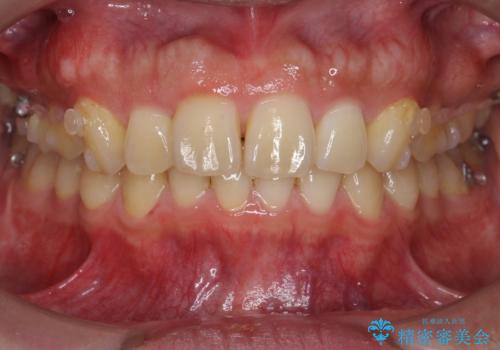

出っ歯を治したい 深いかみあわせ インビザラインで治療

- 前歯の前突を主訴に来院。

上の歯並びが前方にずれていました。

上顎は歯を抜かずに、奥歯を後ろに下げる治療を行っています。

下顎は歯列を拡大して並べました。